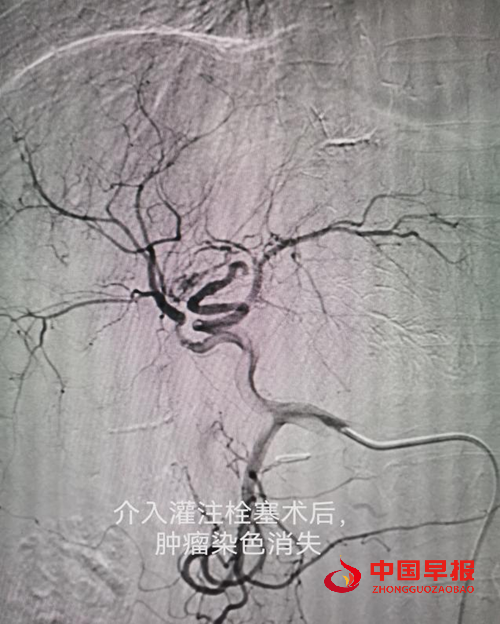

图片2.png

222.png

病例二:李女士,52岁,患胆管癌,经过一次介入微创治疗+三次细胞治疗+靶向治疗,胆管癌大部分消失,临床症状大部分好转,暂处于NED状态。